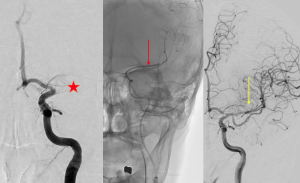

| 脳血管内手術による機械的血栓除去術 |

★ 左中大脳動脈が血栓により閉塞 →血栓回収用のカテーテルを挿入 →吸引後再開通を得る |